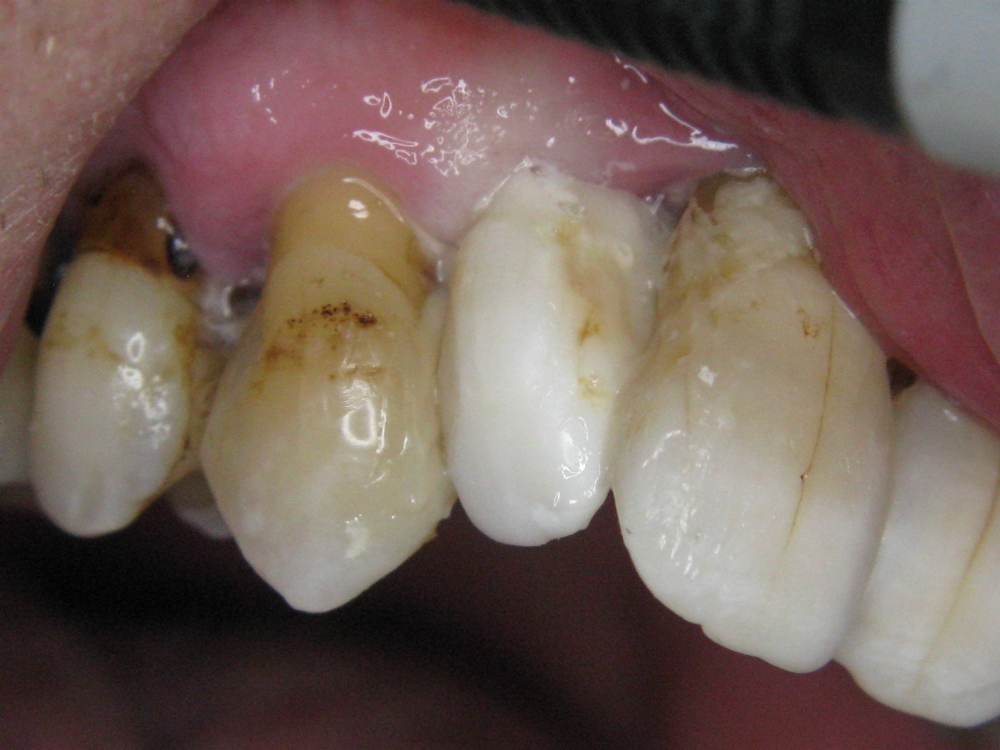

Verlagerung des Frontzahns 1.2

Der 62-jährige Herr aus Amsterdam, von Beruf Berufsberater, kam heute mit einem abgebrochenen Vorderzahn, der Größe 1,2, zu uns

Der 61-jährige Herr aus Amsterdam, von Beruf Karriereberater, stellte sich heute mit einem abgebrochenen Schneidezahn 1.2 vor und bat um eine Wiederbefestigung. Den herausgefallenen Zahn hatte er in Absprache in einem Fläschchen mit Wasserstoffperoxid-Spüllösung aufbewahrt, was die auffallend weiße Färbung erklärt.

Nach ausreichender Behandlung mit Healozon wurde ohne vorheriges Ätzen Coltene One Coat 7 aufgetragen, anschließend One Coat mit Aktivator. Der Stumpf wurde mit dem dualhärtenden Bulk-Komposit Coltene Fill-Up (Zwei-Komponenten-System) wiederaufgebaut. Zusätzlich erfolgte eine Adhäsivverbindung mit den benachbarten Zähnen 1.3 und 1.1. Nach einer 5-sekündigen Lichtpolymerisation härtete die Restauration für weitere drei Minuten selbstständig aus. Palatinal wurde noch etwas nachmodelliert. Eine Politur wurde auf eine Folgesitzung verschoben.

Die Haltbarkeit der Restauration wurde mit 40 Jahren angesetzt, was als realistisch eingeschätzt wird. Für Fachkreise: Eine solche Rekonstruktion ist ohne den Einsatz von Healozon nicht möglich.